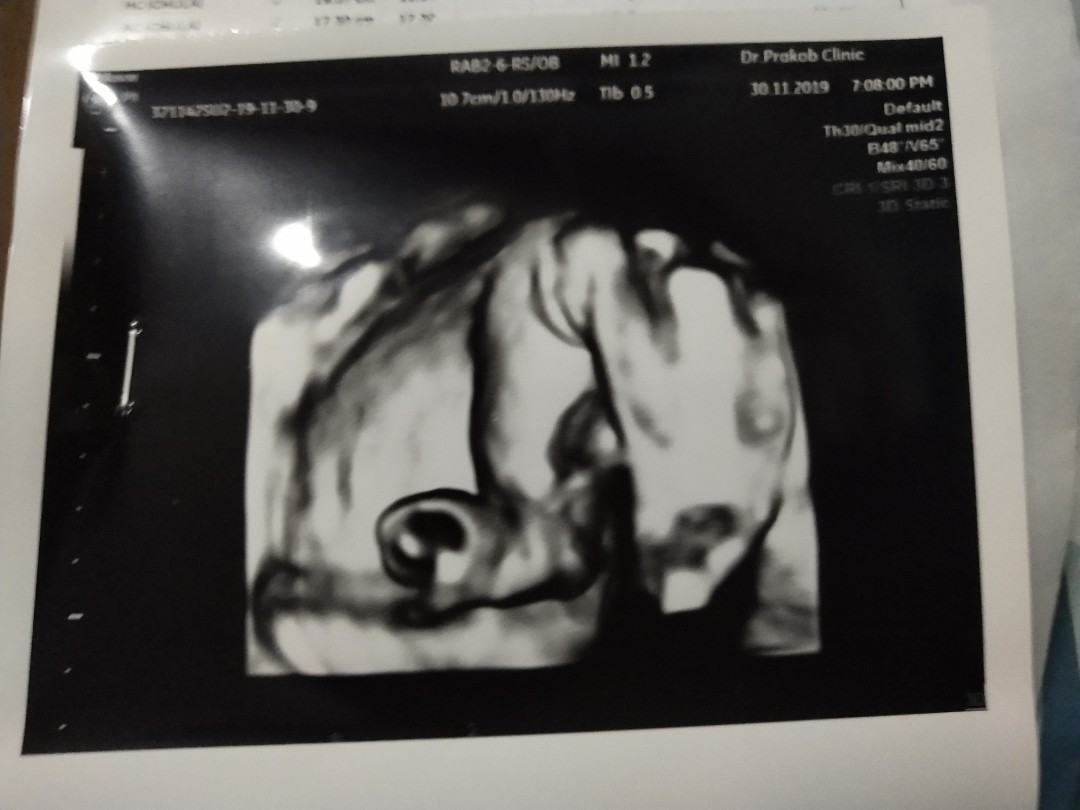

บ้านนี้มาเป็นแท่งเลยค่ะ 😄😊

ทั้งพวงทั้งแท่งเลยคร้าบ 😊😁

คุณหมอบอกผู้ชาย100%คร้าบบบ😂😂